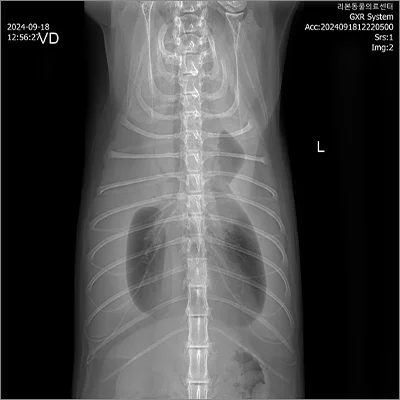

📍 폐엽절제

폐엽절제 전

폐엽절제 후

정확한 진단과 수술로 삶의 질을 회복합니다